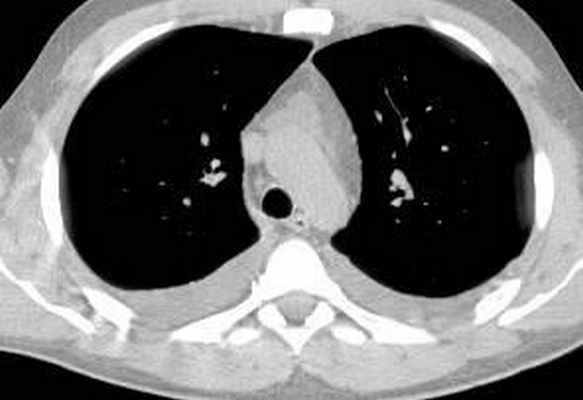

Больной С., 33 г., по профессии электромонтажник, поступил в НМХЦ им. Н.И. Пирогова 5 февраля 2007 г. с жалобами на одышку при незначительной физической нагрузке, кашель с трудноотделяемой мокротой слизистого характера, общую слабость, похудание на 10 кг, субфебрильную температуру тела. С 2000 г. у пациента диагностировали хронический ринит, синусит, полипоз носа. Для купирования затрудненного носового дыхания последние 3 года применял кортикостероидный назальный спрей. В связи с возникновением приступов удушья 2006 г. в НИИ аллергологии и иммунологии диагностирована бронхиальная астма среднетяжелого течения. Назначена терапия симбикортом с положительным эффектом. Ухудшение состояния с декабря 2006, когда появились субфебрильная температура тела, приступы затрудненного дыхания, одышка при физической нагрузке, снижение аппетита. При КТ органов грудной клетки, выполненной амбулаторно 25.01.07г.: лимфаденопатия средостения (лимфоузлы до 2-2,5 см) с образованием конгломерата размером 38 х 40 х 50 мм (рис. 1), снижение прозрачности легочной ткани по типу «матового стекла» (рис. 2а), диффузное уплотнение интерстициальной ткани (рис. 2б), двусторонний гидроторакс. Заподозрена опухоль переднего средостения в связи, с чем пациент госпитализирован для морфологической верификации диагноза.

| Рис. 2. КТ грудной клетки: а - снижение прозрачности по типу “матового стекла“, б - диффузное уплотнение интерстициальной ткани. | |